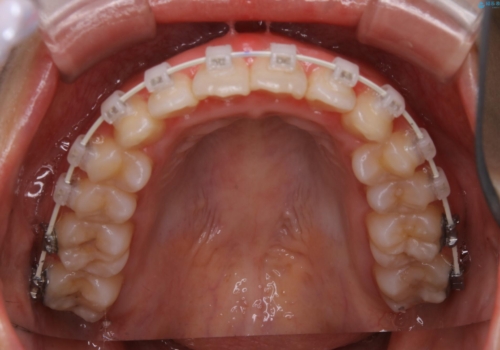

- 矯正装置

- ワイヤー審美装置

インビザラインは20時間以上の装着を厳守して頂くことで治療効果が期待できる治療となります。固定式のワイヤー装置に切り替えることで短期間で歯並びを整えることができ、大変喜んでいただけました。